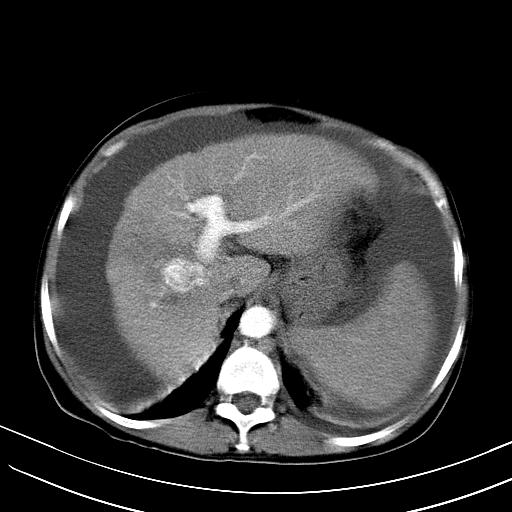

标题: CT23697:肝癌并肝动静脉漏? [打印本页]

标题: CT23697:肝癌并肝动静脉漏?

肝动静脉漏,动脉期肝动脉及门静脉内均可见造影剂……

1)肝右叶肝癌并肝动静脉漏。2)肝硬化,腹水。3)胆囊炎。

肝右叶肝癌并动静脉漏,肝硬化,腹水。

1)肝右叶肝癌并肝动静脉漏 门v右支瘤栓伴海绵样变。2)肝硬化,脾大 腹水。3)胆囊炎。门v高压.

右叶肝癌并肝动静脉漏(动脉期肝动脉及门静脉内均可见造影剂),肝硬化,腹水。(胆囊壁水肿)

1)肝右叶肝癌,考虑并发肝动静脉漏。扫描时间好像慢了。2)肝硬化,门脉高压、脾大、腹水。